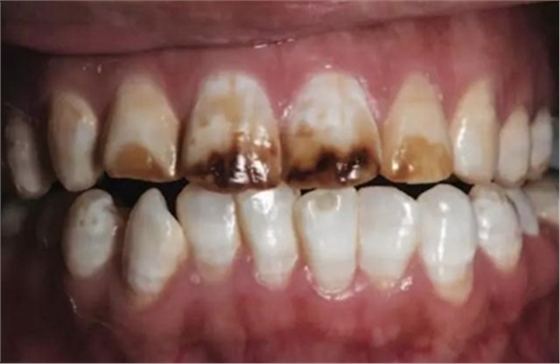

一28歲女性患者來我院修復(fù)科就診,主訴為前牙嚴(yán)重的牙齒著色和缺損十余年,要求改善牙齒的美觀。臨床檢查表明該患者有重度氟斑牙,極大的影響了前牙美學(xué)。

考慮到患者為年輕人,保守治療方法比傳統(tǒng)侵入性治療手段更為合適。術(shù)前牙周治療預(yù)防牙齦炎癥和改善牙齦健康狀態(tài),隨后聯(lián)合采用釉質(zhì)打磨、牙漂白和樹脂滲透來處理牙釉質(zhì)表面。